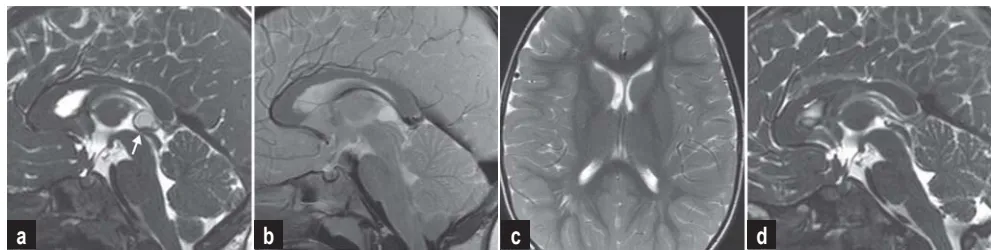

影像学检查显示:矢状位CISS序列可见导水管入口明显狭窄,IRTSE序列显示导水管内脑脊液流动正常,术前T2加权像显示侧脑室宽度正常,术后影像确认囊肿完全切除。

传统认为手术干预仅适用于囊肿压迫脑脊液通路导致脑室扩大的病例。然而临床存在部分脑室大小正常但症状明显的患者群体。发病机制在于囊肿位于导水管入口附近,在咳嗽、用力或体位改变时可能一过性阻塞脑脊液循环,引起颅内压骤升,出现阵发性症状。

CISS序列清晰显示囊肿与中脑导水管的关系

诊断重点并非囊肿绝对尺寸,而是其对关键结构的压迫程度,特别是导水管受累情况。